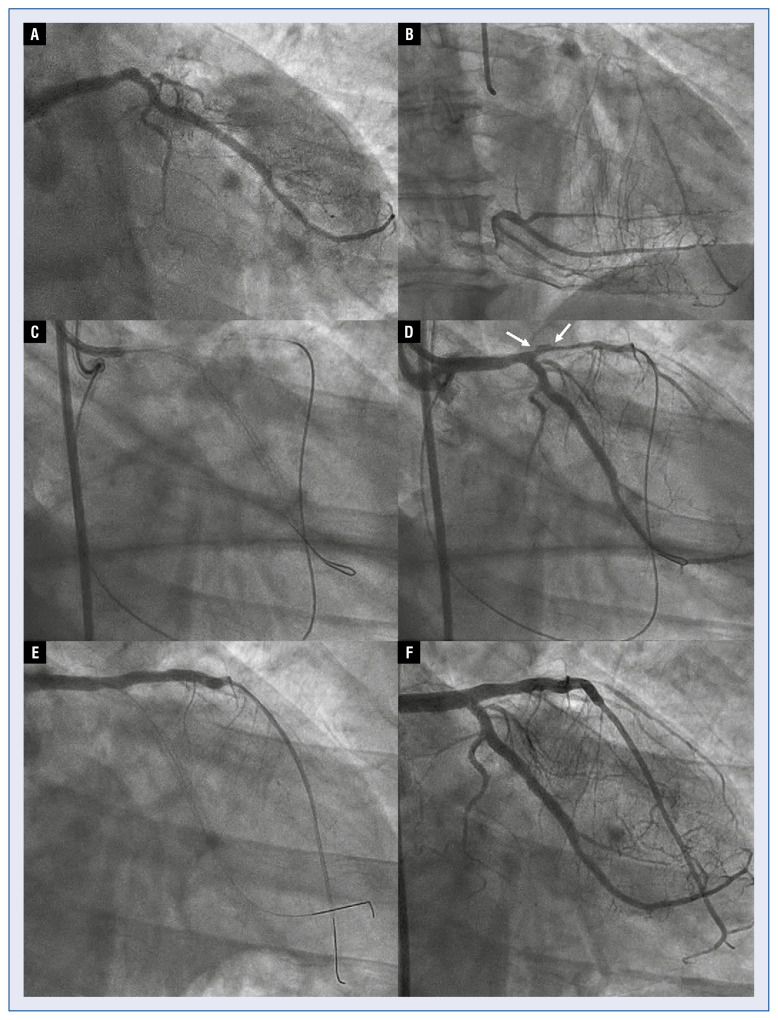

背景:本研究的目的是描述内膜下移位(SIS)的机制,标准化诊断标准,并使介入治疗界对这一现象更加敏感。慢性全闭塞(CTO)的经皮冠状动脉介入治疗(PCI)是复杂的分岔病变累及CTO段或其邻近。在CTO PCI时冠状动脉内装置的斑块外扩张可以通过内内侧皮瓣将剥离平面扩展到分叉上,从而导致相应的侧支或主支受压。本文首次描述这种现象,并将其命名为内膜下移位。方法:来自3个国际CTO PCI高容量中心的经验丰富的CTO操作员回顾性检索其个人记录中的典型SIS病例,总结关键特征并提出诊断标准。结果:本组病例共7例,CTO PCI行血管内显像(2例)或间接血管造影征象(5例)。5例由支架扩张引起,1例由球囊膨胀引起,1例因血管造影警示信号而流产。在4例中,SIS导致分支完全闭塞,无论何时尝试球囊都难以膨胀。4例需要紧急救助干预,2例左支闭塞,导致心脏指标升高。结论:内膜下移位是CTO分支值得注意的并发症,可能导致相关侧甚至主分支闭塞。建议在支架植入前进行冠状动脉内成像以了解组织平面。这种现象的一些违反直觉的特性,比如它对气球的耐火性,必须由CTO操作员了解才能有效解决。

Background: The aim of this study was to describe the mechanism of subintimal shift (SIS), standardise diagnostic criteria and sensitise the interventional community to this phenomenon. The treatment of chronic total occlusions (CTO) by means of percutaneous coronary intervention (PCI) is complicated by bifurcation lesions involved in the CTO segment or adjacent to it. Extraplaque expansion of intracoronary devices during CTO PCI may extend the dissection plane over the bifurcation with the consequential side or main branch compression by an intimo-medial flap. This phenomenon is hereby described for the first time and named subintimal shift.

Results: The series comprised 7 demonstrative cases, illustrating SIS by intravascular imaging (2 cases) or indirect angiographic signs during CTO PCI (5 cases). Five cases were triggered by stent expansion, 1 by balloon inflation and 1 case was aborted after angiographic warning signs. In 4 cases, SIS resulted in total occlusion of a branch, refractory to ballooning whenever attempted. Four cases required bailout intervention and in 2 cases the branch was left occluded, resulting in a rise of cardiac markers.